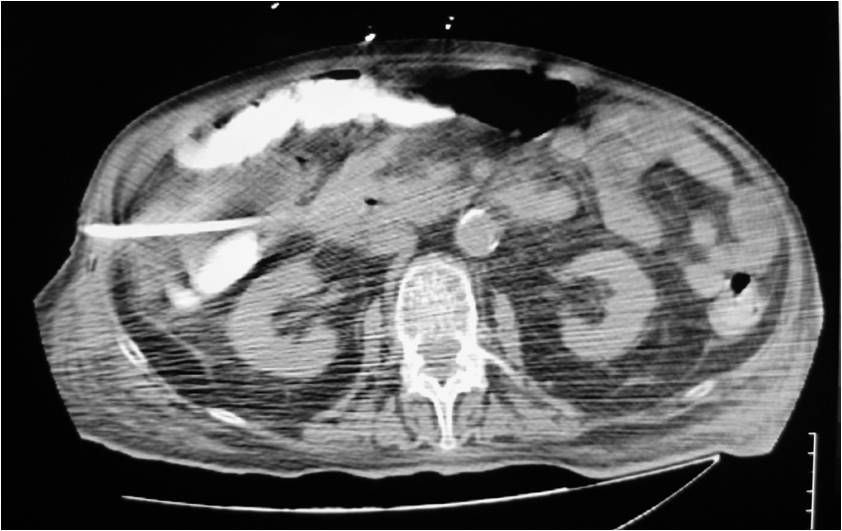

- Abscess post left hemicolectomy

- Successful placement and drainage